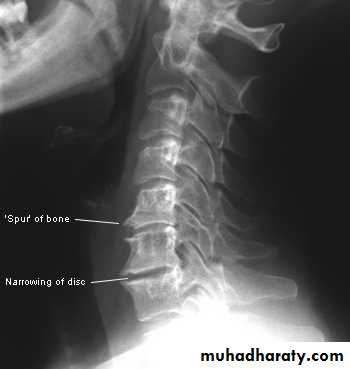

Five hallmarks:* Narrowing of joint space, usually asymmetrical

*Subchondral sclerosis

* Subchondral cysts (true cysts or pseudocysts)

* Osteophytes

* Lack of osteoporosis

* Lower cervical and low lumbar spine are most comonly affected.* Osteophytes may encroach on neural foramina (best seen on oblique views).

Cervical spondylosis